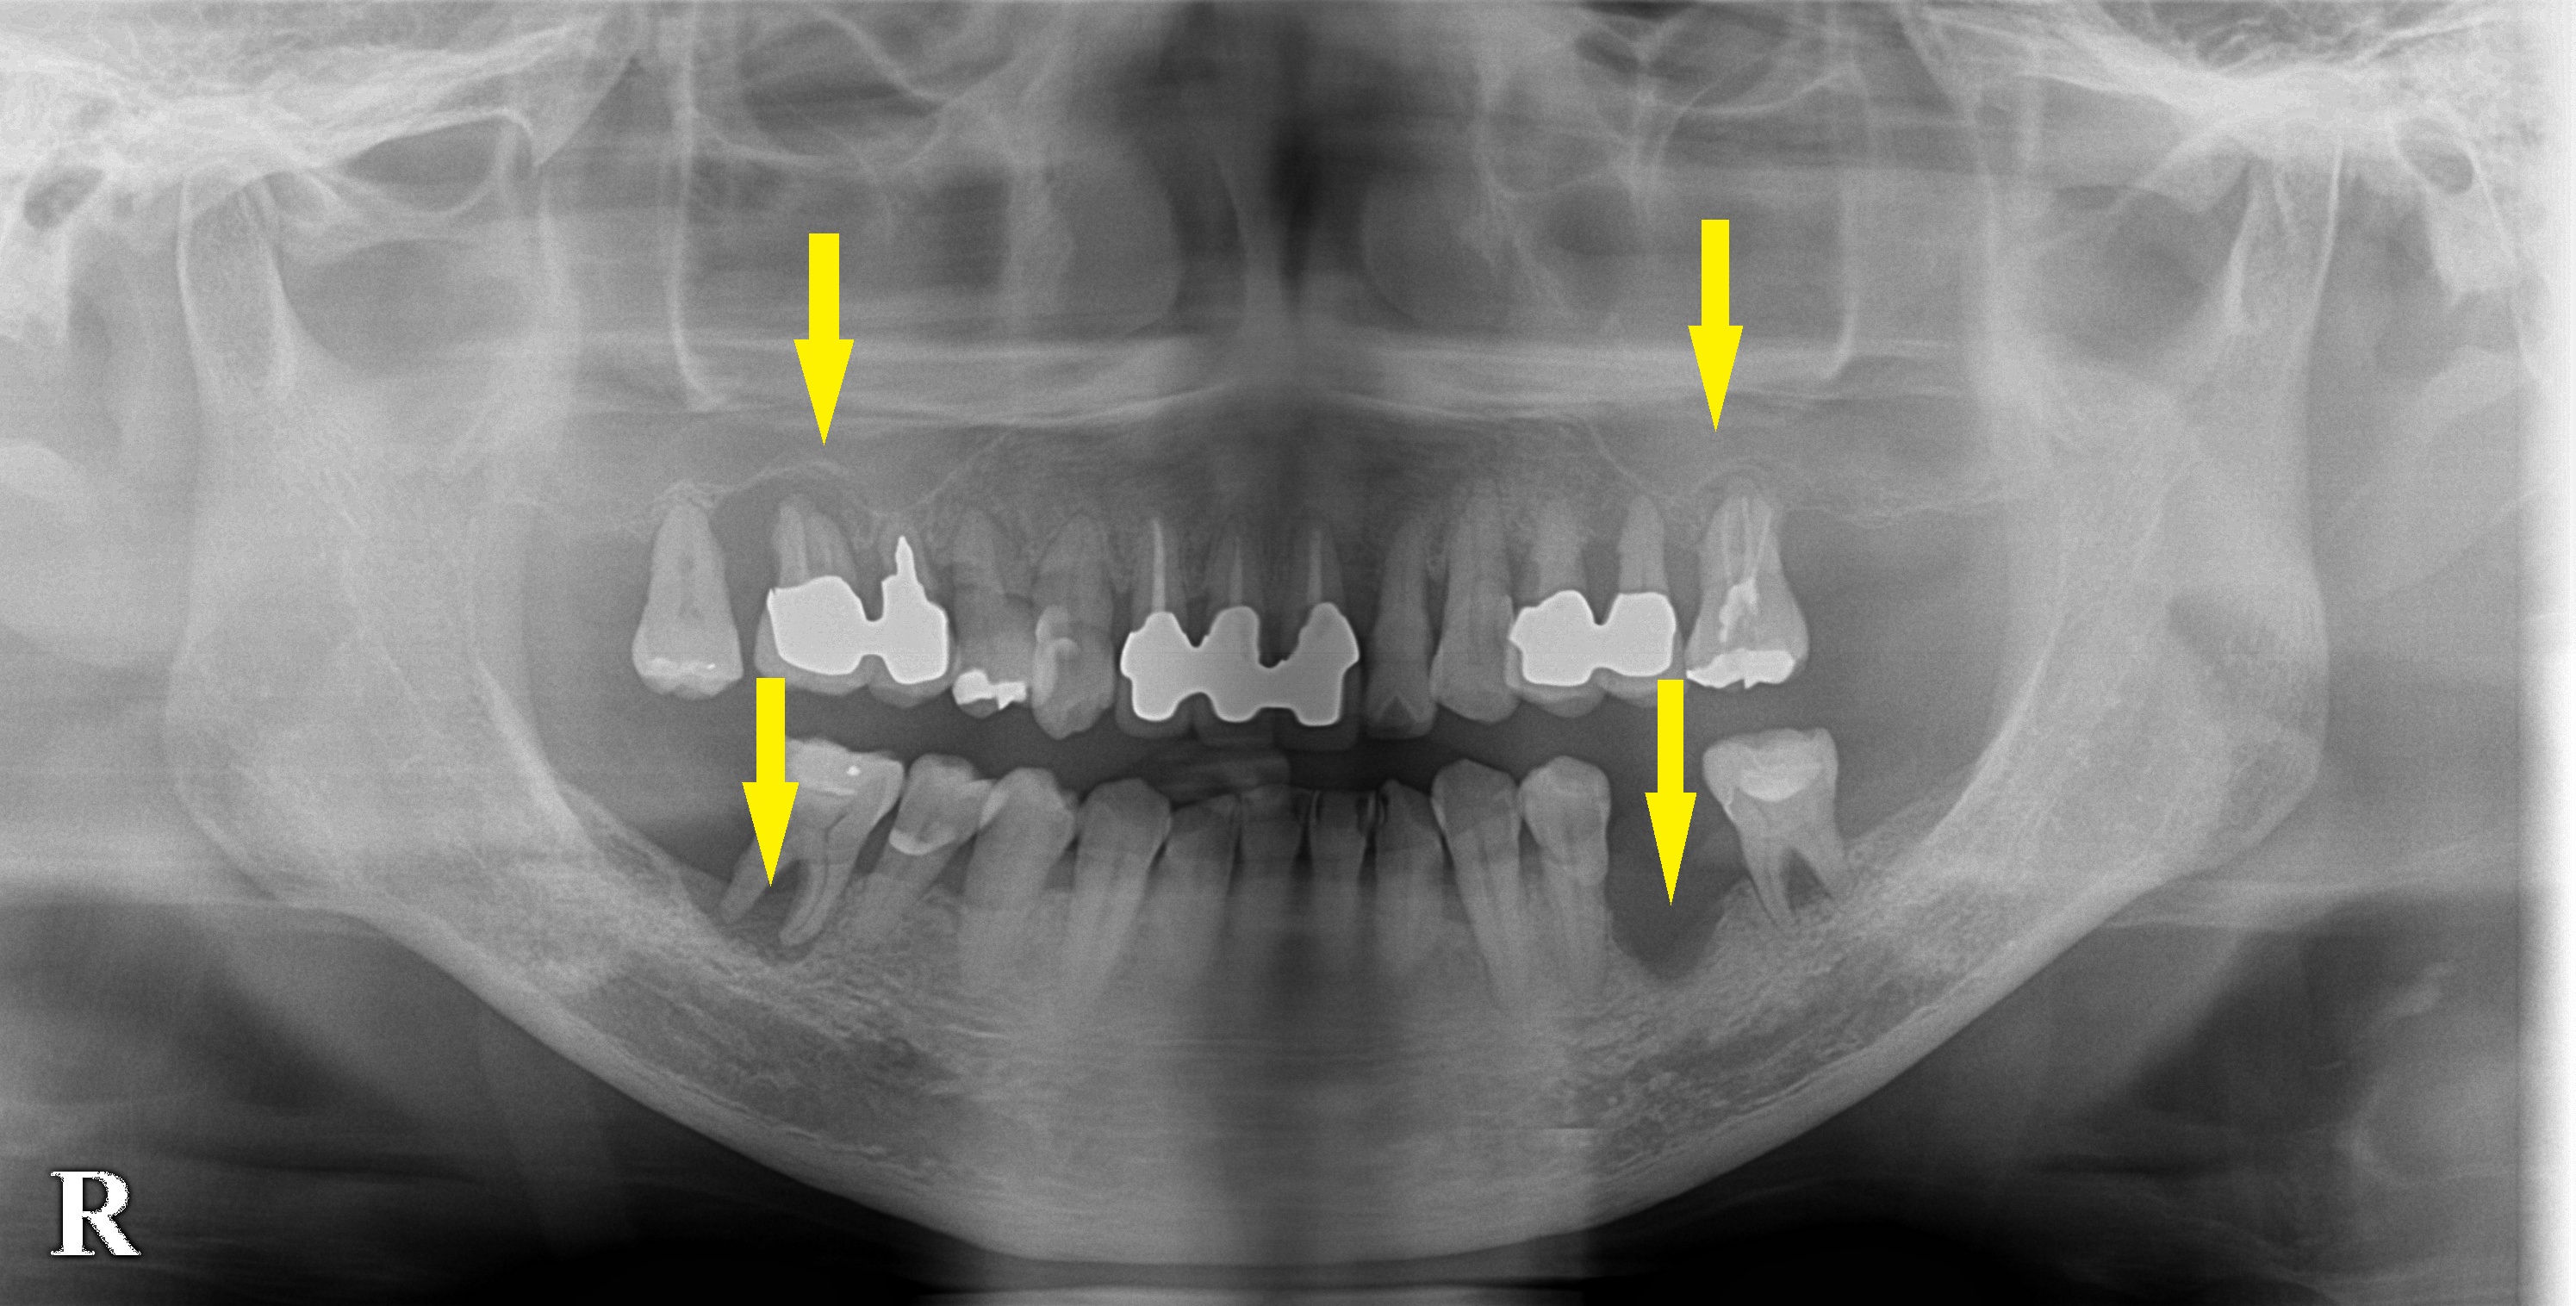

上下左右とも大臼歯が、重度の歯周病で大きく骨が吸収されてしまっている患者様です。

確かに、上顎の臼歯部は、紙のように薄い骨しかなく、下顎もかなり神経の近くまで骨が吸収されてしまっていました。